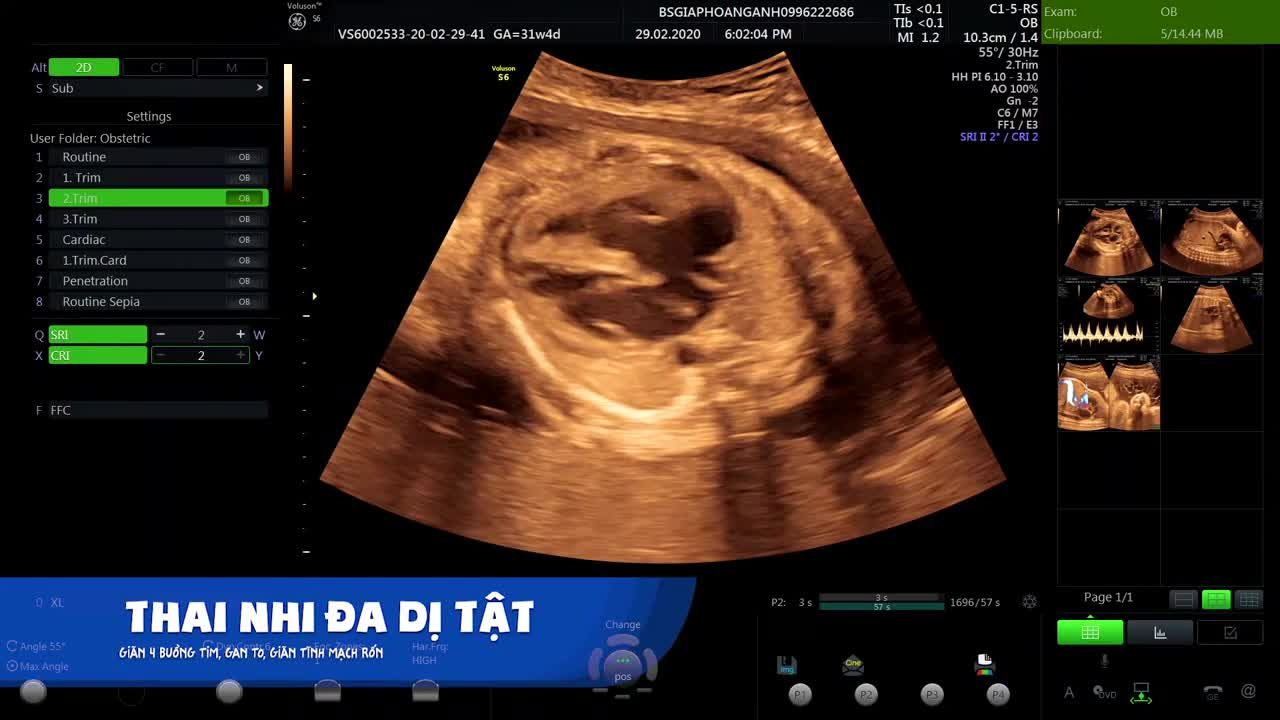

Siêu âm có kết quả thai tim bị to, nhu mô ruột non tăng âm

Hôm trước em có đi siêu âm có kết quả là thai bị tim to như này. Bác sĩ tư vấn cho em với ạ. Em đã có 1 cháu 5 tuổi khoẻ mạnh rồi ạ. Trước đó 2 vợ chồng đã đi khám và không mang ghen thalassima .